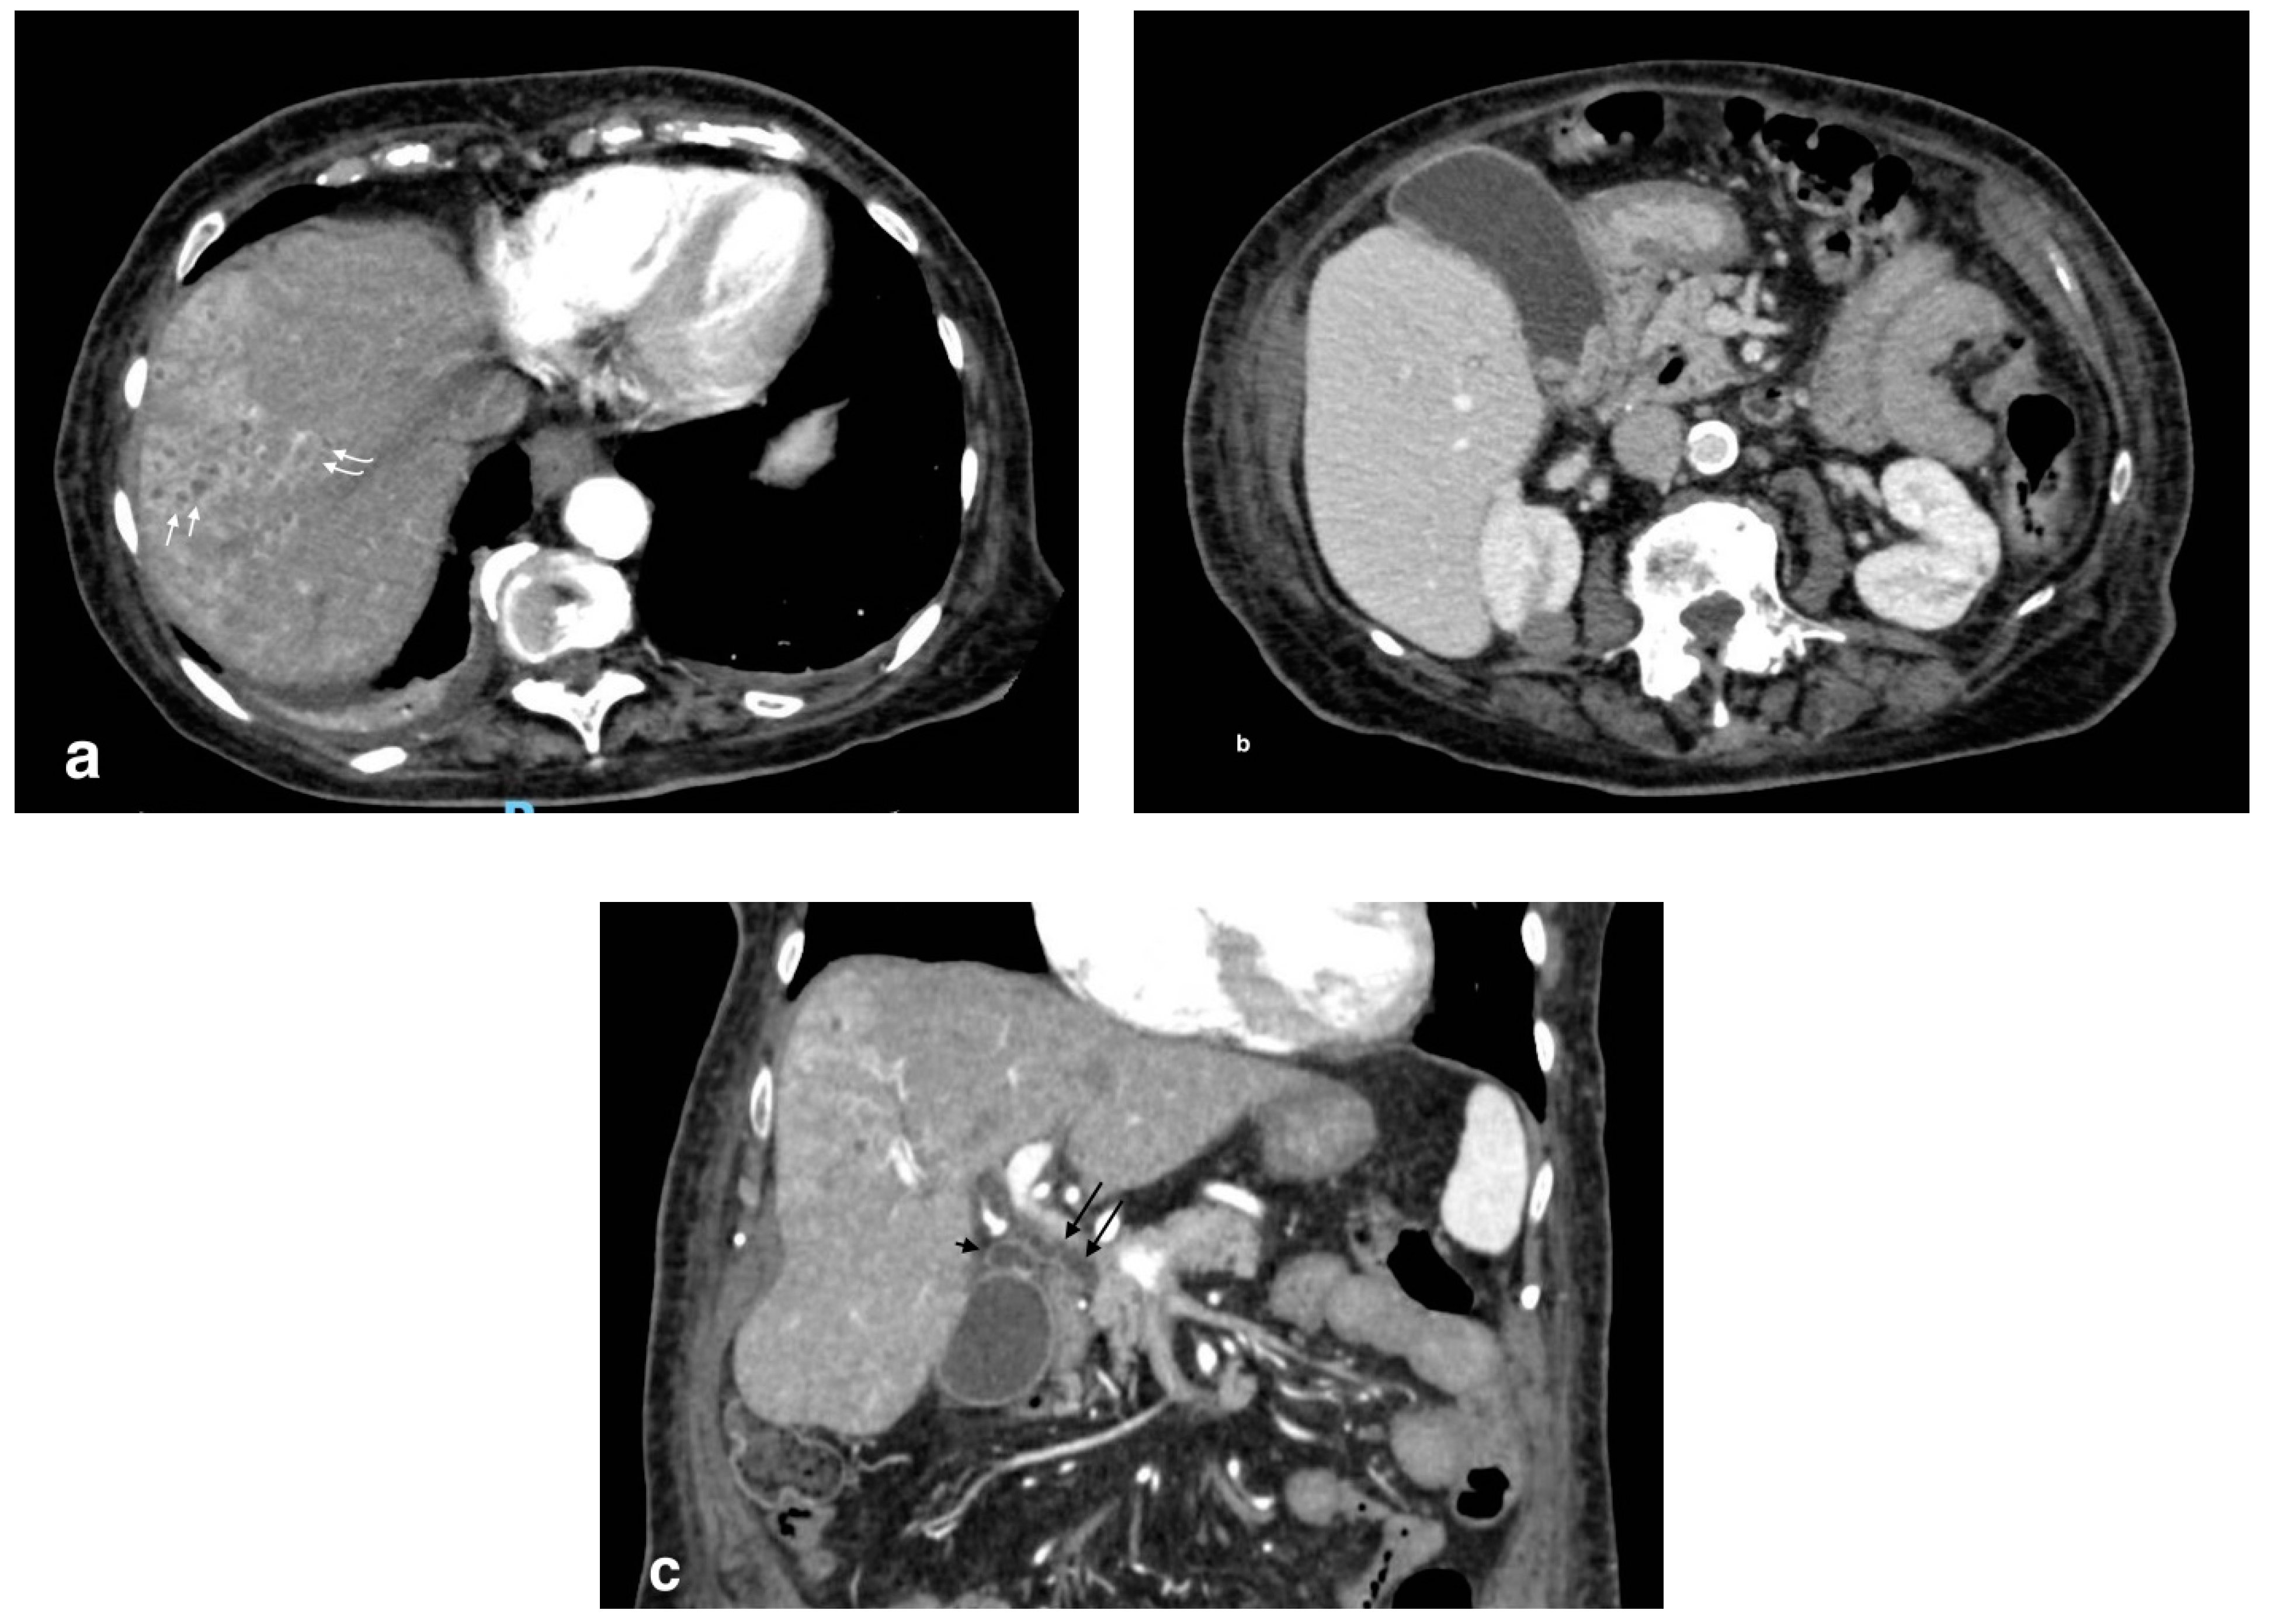

Figure 8.

Pericholecystic abscess: (a) axial images show acute cholecystitis findings with wall thickening and hyperdensity; (b) a hypoattenuated sovracholecistic collection (white arrows) due to hepatic pericholecystic abscess; (c) sagittal image evidences the proximity of the two structures (abscess: black arrow; cholecyst: white arrow).

Figure 9.

Liver abscess with pylephlebitis: (a) CT arterial phase; (b) CT portal phase. In the right lobe, V segment, a large hypodense collection with hypoattenuating halo due to intrahepatic abscess (black arrows, (a,b)) with the presence of a hypodensity within the left portal vein lumen due to thrombosis and hyperdensity of portal walls indicative of pylephlebitis better defined in CT portal phase (b) (white arrow).